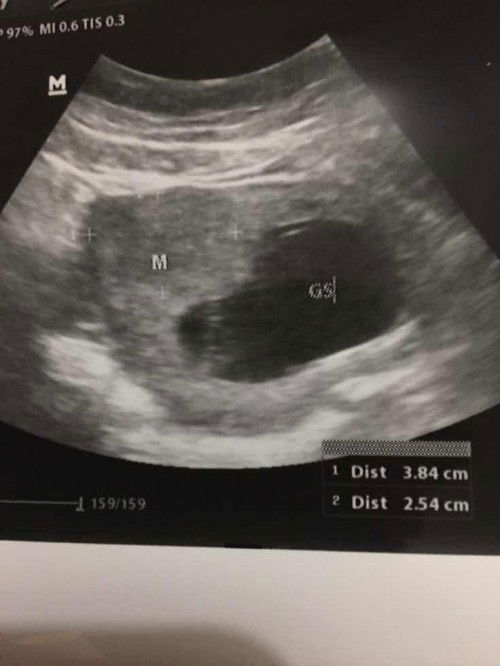

Hallo mom, disni aku mau sedikit cerita tdi aku baru usg di kehamilan aku 11w tapi kata dokter aku ada miom😣 sedikit sedih si dengernya tapi kata dokter si gpp. Palingan resiko besarnya lahiran checar, Alhamdulilah bayi aku sehat dan berkembang dgn baik. disni mom ada gak yg kya aku hamil terus ada miom. Klo ada boleh dong cerita. Kta dokter jng di pikirin insyallah gak kenapa2. Tpi mau gmn ya mom maklum baru hamil anak pertaman jdi agak kaget si denger kata miom Biar aku jga gak kepikiran Makasih mom🥰#ingintahu #pleasehelp